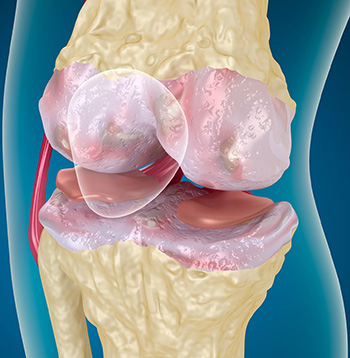

- Osteoarthritis. Ebben az esetben is van, porc sérülés.

Térd fájdalom és duzzanat, amelynek duzzanat típusú, gyakran az eredménye, ilyen betegség, mint az ízületi gyulladás. Tény, hogy jön a gyulladás, ami a szervezet fertőzésre adott válasza. A legtöbb esetben a károsító szervezetek a véráramba kerülnek és nyirokrendszeri keresztül a sérült lábát. Ezért, miután sérülés fontos, hogy azonnali orvosi ellátás és a vizsgálatot elvégezni.

Fertőzés vezethet jelentős megsemmisítése ízületi struktúrák